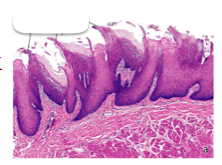

Name this structure

Circumvallate papillae of specialized oral mucosa

Filiform papillae of specialized oral mucosa